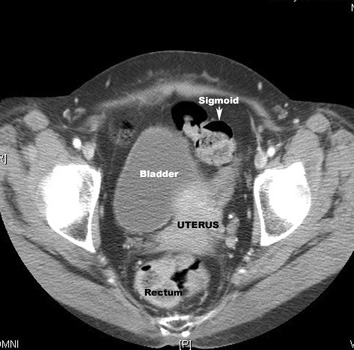

ct pelvis anatomy pelvic uterus hysterectomy section cross bladder inside organs space body sigmoid left happens woman lumen meded obgyn